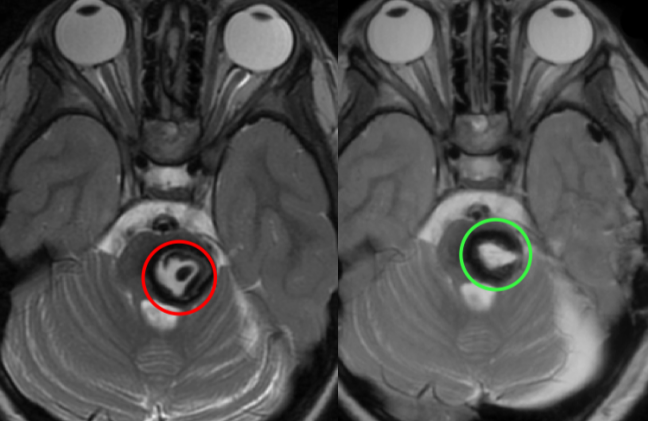

术后立即进行影像学复查确认:病变实现镜下全切,手术区域没有新发出血,没有明显水肿,瘤腔内可见止血材料正常显影。

出院时,晶晶术前的头痛症状完全消失,四肢肌力正常,感觉功能正常,视力没有受损,没有呼吸抑制等手术相关并发症。此外,术后影像学确认全切后,晶晶不需要进一步辅助治疗,可以恢复正常的日常生活和学习。

值得注意的是,术后复查MRI显示:脑干形态保持良好,受压区域逐渐恢复正常。这印证了早期干预对功能保护的价值。如果继续等待反复出血,可能造成不可逆的神经核团损伤。